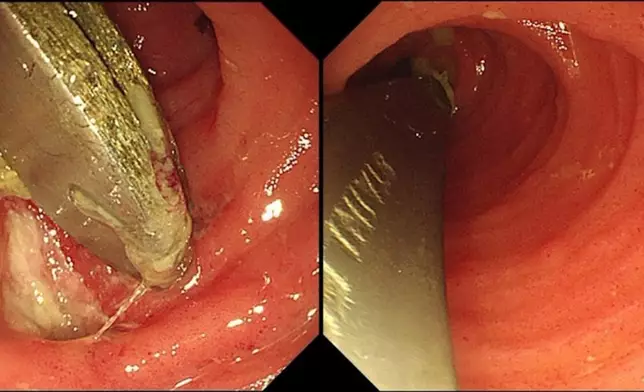

入院後,醫生為張先生再次安排CT及腸鏡檢查,確認兩把匙羹卡在回腸末端,周邊黏膜已出現潰瘍變化,隨時有腸道穿孔風險,情況相當危險。由於異物長約12CM,且位處腸腔較狹窄的小腸位置,取出難度甚高。醫療團隊經過近1小時的細緻操作,最終成功以內窺鏡將兩把匙羹完整取出,令患者免卻接受剖腹手術之苦。